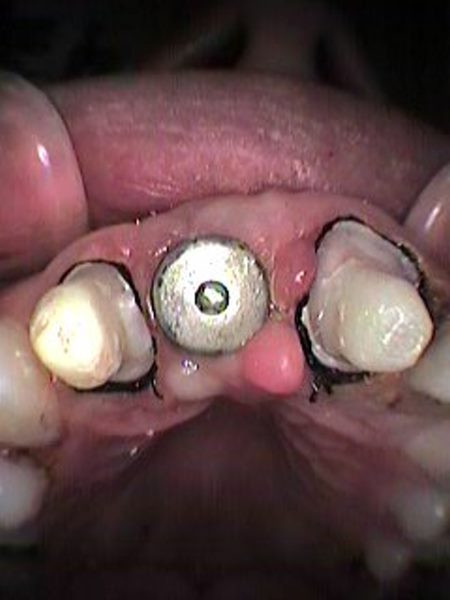

Vista oclusal inicial

Se remueve tornillo de cicatrización

Vista clínica implante